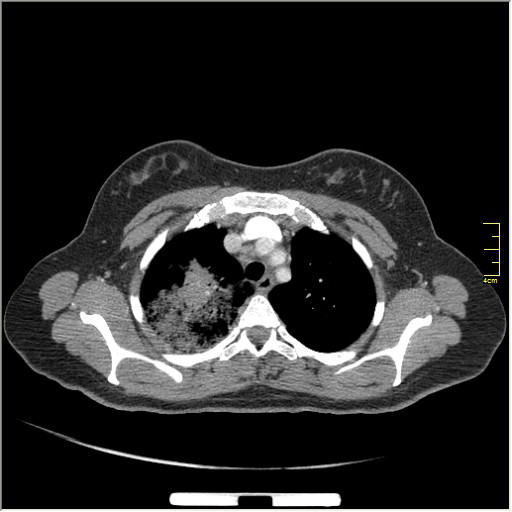

Прошу прощения что задержался с публикацией КТ. Последняя реконструкция в сагиттальной проекции специально для Валентина Львовича! Я кстати тоже ценю сагитталы больше чем корональные реконструкции, они более "анатомичны". На КТ, мы вдобавок к легочным изменениям, нашли небольшой плевральный выпот на стороне поражения.

Гм, вопрос конечно интересный. Если бы не два дополнительных очага в правом 6-м сегменте, написал бы пневмония, рентген контроль через 3 недели. А с такими очажками-написал подозрение на TBc. пациентке сделали бронхоископию, взяли материал, сделали ПЦР, и ответ пришёл сегодня положительный: ТУБЕРКУЛЁЗНАЯ ИНФЕКЦИЯ.

Будем спорить! на КТ выпот задний базальный; спереди не видно.

Даже учитывая что пациент при рентгенографии стоял; жидкость под силой тяжести должна была "стечь" кзади. Если бы этот выпот был осумкован, на КТ он не должен бы; изменять свое положение. До 100 мл жидкости в плевральных полостях могут не визуализироватся на при рентгенографии, в этом вопросе приоритет за УЗИ. ИМХО.

Спасибо Валентин Львович, взаимно. Вы относительно правы. На КТ определяются микст изменения: алвеолярная консолидация, плотности по типу матового стекла, микро-кавитации и сохранённая воздушная бронхограмма. Учитывая два очага в шестёрке и локализацию: TBc должен быть обезательно включён в диф. диагноз.

Тактика далее:

1. бронхоскопия-промывные воды (или другой материал)-лабаратория-ПЦР.

2. пункция выпота под УЗИ-лабаратория-ПЦР.